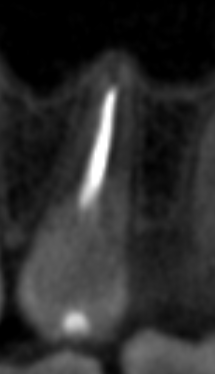

Вчера сделал КТ и стало понятно, что в двух корнях выведен материал за верхушку что аж у корней шляпки появились, а другой корень недопломбирован до конца на несколько миллиметров. Я читал что материалы выводить за апекс в принципе нельзя и это чревато, неужели пульсация над бровью и в области виска связана с этим? Он же и после удаления зуба там останется, как я понял. Где этот материал находится судя по снимкам? Не может ли он как-то влиять на тройничный нерв (не разбираюсь с этим)?

Screenshot_4.png.5e7921a698b28cc04edfe2a9ef1ab7c6.pngScreenshot_5.png.3786d148a30936dc0c8bb6475d7b25c7.pngScreenshot_6.png.cac5adb8499290207c4c9a6019795985.pngScreenshot_7.png.c63e3bf191b149a107f5b4664370a2df.png

Подскажите, пожалуйста, что тут можно сделать и насколько опасен этот выведенный материал. Вроде бы пломбировали Thermafil AH+.